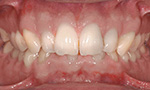

Zahn- und Kieferfehlstellungen

Zahn- und Kieferfehlstellungen können genetisch bedingt sein, sie können aber auch im Laufe der Jahre, z.B. durch Fehlfunktionen, entstehen oder als Kombination von beidem auftreten. Bei einer korrekten Zahnstellung und Kieferlage passen Ober- und Unterkiefer in allen drei Raumebenen perfekt zusammen.

Die häufigsten Fehlstellungen

Nach Prüfung der Funktionen des Gebisses, wie zum Beispiel des Ineinanderpassens der Zahnreihen oder der Funktion des Kiefergelenks, steht fest, welche der folgenden Fehlstellungen vorliegt: